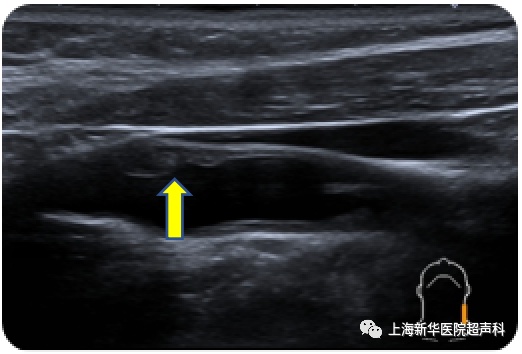

颈动脉斑块就是血液常年在血管里不断的流动,血管里的脂质物质沉积在血管壁上,就逐渐形成了斑块。简单来说颈动脉就像水管,时间长了容易长水垢,最终会导致狭窄和堵塞。

颈动脉斑块